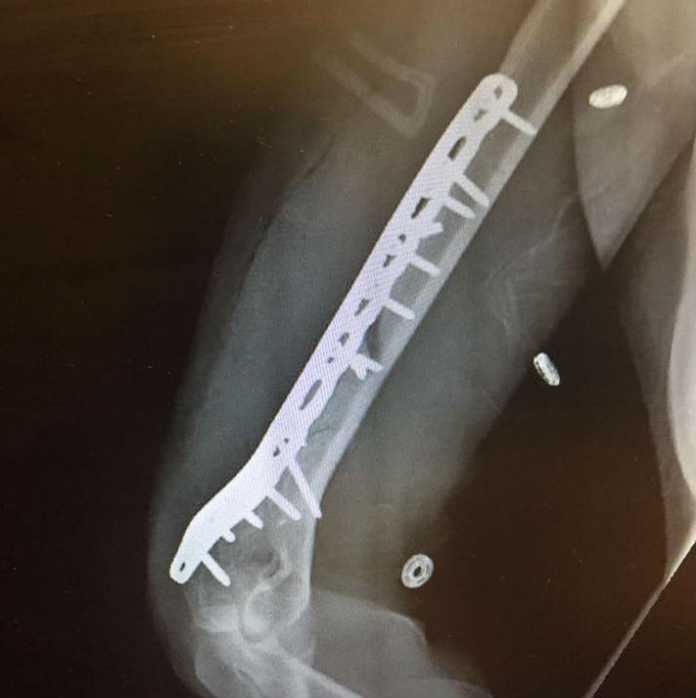

KO – E’ tutto vero, insomma, come ha confermato lei stessa sui social informando i 2.000.000 di tifosi che la seguono: «Sfortunatamente giovedì sono caduta mentre mi stavo allenando in superG, fratturandomi gravemente l’omero destro. Sono stata subito operata a Vail. L’intervento è stato eseguito con successo e tutti si sono presi cura di me. Tornerò sulle piste il più presto possibile, come ho sempre fatto. Grazie per il continuo affetto e supporto nei mie confronti, significa tanto per me. Non so perché mi accadano queste cose, ma sono un alottatrice e non mi farò buttare a terra #NeverGiveUp». Ovvero, mai mollare. Firmato, Lindsey, sulla sula pagina di Facebook.